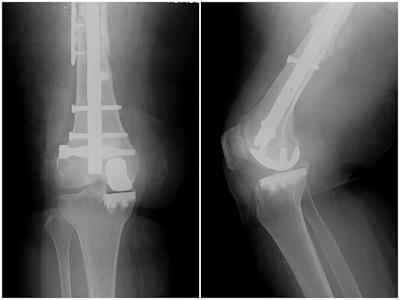

A partial knee arthroplasty is the surface replacement of only the diseased compartment of the knee. Typically more common on the inner (medial) side of the knee, the diseased cartilage and the underlying bone is covered with metal and polyethylene implants. (Figure 1).Figure 1a,b: Comparison of a total and partial knee replacement.